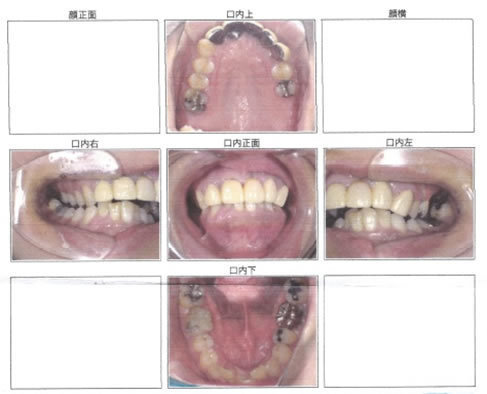

歯周病治療を他院で受けているが改善しないということでご来院(女性・50代)

治療期間

9/19~11/10

治療費用

100,000円(税別)

治療内容

エクセレントぺリオ一連の流れ

治療前

お口の中全体的に歯周病が進行し、

歯ぐきが下がってきていました。

治療後

全ての歯がきれいにクリーニングされ、

歯ぐきの状態も改善しています。